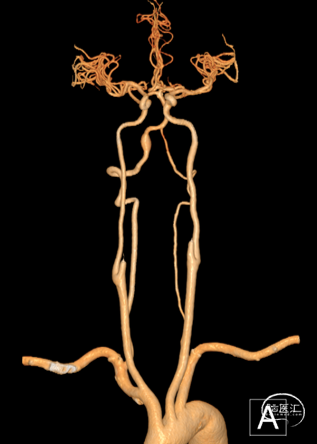

CTA:

右侧椎动脉(优势侧)V4段梭形动脉瘤,

左侧椎动脉纤细,后交通动脉未显影。

影像科提供的重建图像就像美颜照片,虽然好看,但丢失了诸多细节。

我们使用影像工作站重建的图像能够看到更多细节:

动脉瘤处有明显的凹陷,考虑为动脉夹层的内膜瓣;动脉瘤累及小脑后下动脉(PICA)的开口。